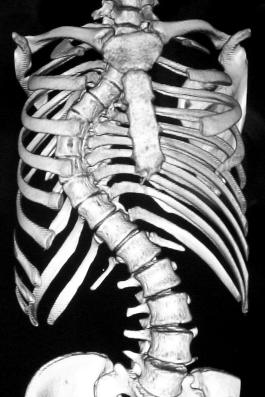

Standing erect Dorso-lumbo-sacral spine PA & Lateral views with planning. CT also done.

Pre op

Pre-op AP